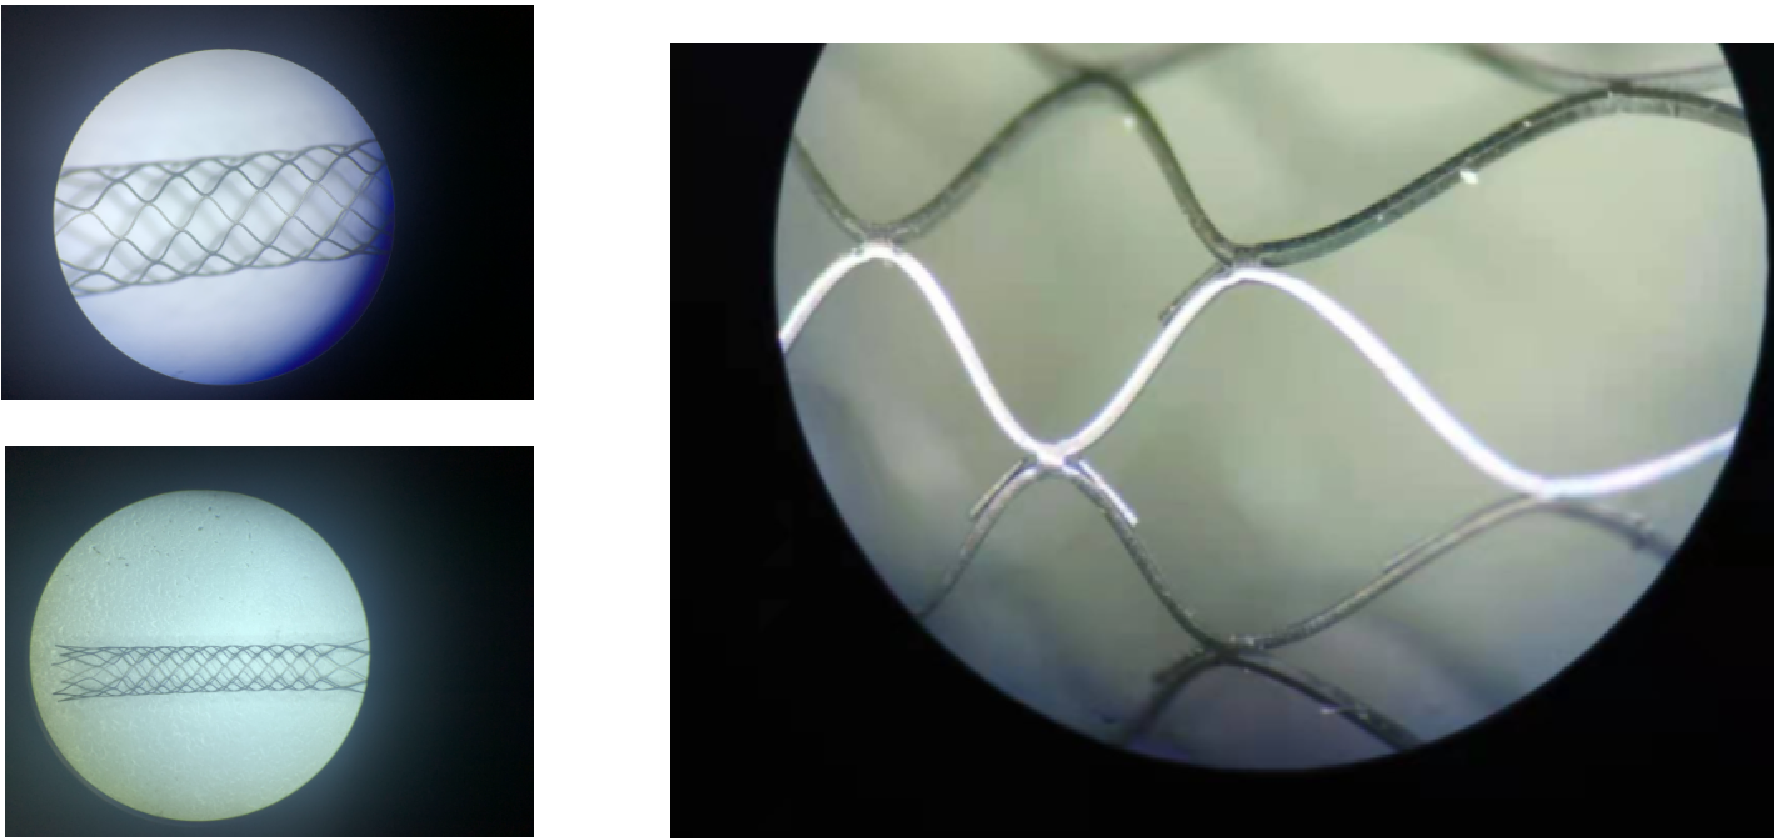

心血管支架喷砂工艺作为植入前确保电化学抛光的稳定性和粗糙度均一的保障,目前被广泛应用并“有保留”的在行业内作为特色工艺和独有工序而存在。

激光切割后有熔渣,毛刺,氧化层及切割去除不完善区域。

支架喷砂工艺:喷砂前

支架喷砂工艺:喷砂后